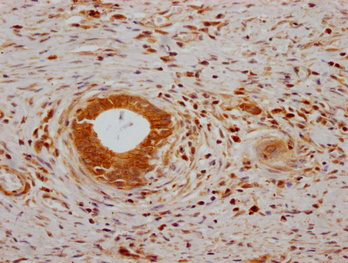

IHC image of CSB-PA614990LA01HU diluted at 1:200 and staining in paraffin-embedded human gastric cancer performed on a Leica BondTM system. After dewaxing and hydration, antigen retrieval was mediated by high pressure in a citrate buffer (pH 6.0). Section was blocked with 10% normal goat serum 30min at RT. Then primary antibody (1% BSA) was incubated at 4°C overnight. The primary is detected by a Goat anti-rabbit polymer IgG labeled by HRP and visualized using 0.05% DAB.